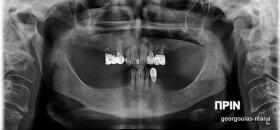

Η ασθενής αυτή είχε παλιές ακίνητες αποκαταστάσεις (γέφυρες) στην άνω γνάθο  κ μια κινητή προσθετική αποκατάσταση (μερική οδοντοστοιχία-"μασελάκι") στην κάτω γνάθο. Ήταν δυσαρεστημένη τόσο με την εμφάνιση όσο και με τη λειτουργία των δοντιών της καθώς παραπονιόταν ότι  είχαν εντονη κινητικότητα ενώ και οι προσθετικές τους εργασιές δεν ήταν σταθερές. Η πρόγνωση των δοντιών κρίθηκε φτωχή με αποτέλεσμα να μην είναι δυνατή η συμμετοχή τους σε μια νεα προσθετική αποκατάσταση με μακροχρόνια διάρκεια. Η ασθενής επιθυμούσε οι νέες αποκαταστάσεις να είναι σταθερές και ακίνητες.  Για το λόγο αυτό αποφασίστηκε η ολική αποκατάσταση της άνω κ κάτω γνάθου με ακίνητες επιεμφυτευματικές εργασίες. Στην αριστερή πλευρά της άνω γνάθου, λόγω μη επαρκούς οστού για την τοποθέτηση εμφυτευμάτων προηγήθηκε επέμβαση ανοιχτής  ανύψωσης ιγμορείου άντρου με τη χρήση πιεζοχειρουργικού μηχανήματος ώστε να δημιουργηθεί το κατάλληλο οστικό υπόστρωμα. Ακολούθησε σε επόμενο χειρουργείο η εξαγωγή των υπάρχοντων δοντιών κ η άμεση τοποθέτηση εμφυτεύματων (άμεση εμφύτευση) κ δύο μέρες μετά η τοποθέτηση προσωρινής εργασίας επί των εμφυτευμάτων (άμεση φόρτιση) με αποτέλεσμα η ασθενής να μη μείνει καθόλου χωρίς δόντια κ να είναι καλυμένη αισθητικά όσο καιρό διήρκησε η εργασία